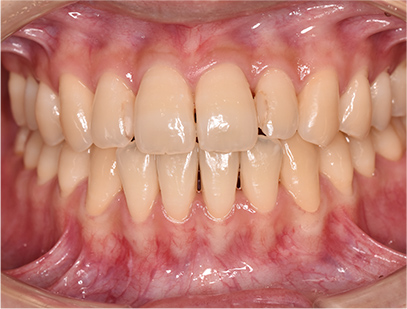

症例01|中学生の男子

前歯部の反対咬合

前歯部の反対咬合と上顎前歯のデコボコを主訴として来院されました。精査、診断の結果「前歯部に叢生を伴う反対咬合」と診断されました。

治療計画

非抜歯にて前歯の再配列、反対咬合の改善を行う事にしました。

治療後

• 正面

治療前の写真と比べると前歯部の反対咬合は改善されて、上顎の前歯部のデコボコも綺麗に並べる事ができました。

また口元は上の歯が前に出たために口唇がへこんでいたことも改善されて男らしい綺麗な口元に改善できました。 治療期間は2年と6か月を必要としました。